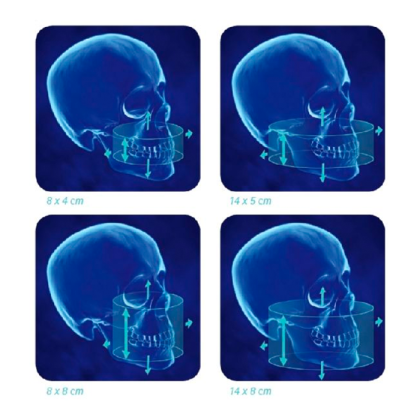

Прибор оснащен передовым датчиком из аморфного кремния, который предоставляет точное получение данных за 8,9 секунд сканирования, а время реконструкции 3D-модели составляет около 20 секунд. Базовый режим сканирования охватывает область размером 8,5x8,5 см, что позволяет детально анализировать зубные ряды и челюсти. Для более широкого охвата доступны расширенные режимы с полем до 23x17 см.

| Размер изображения | минимально 8x8 см, в стандартном режиме 16x13 см, в расширенном режиме (Extended diameter scan) 23x17 см |